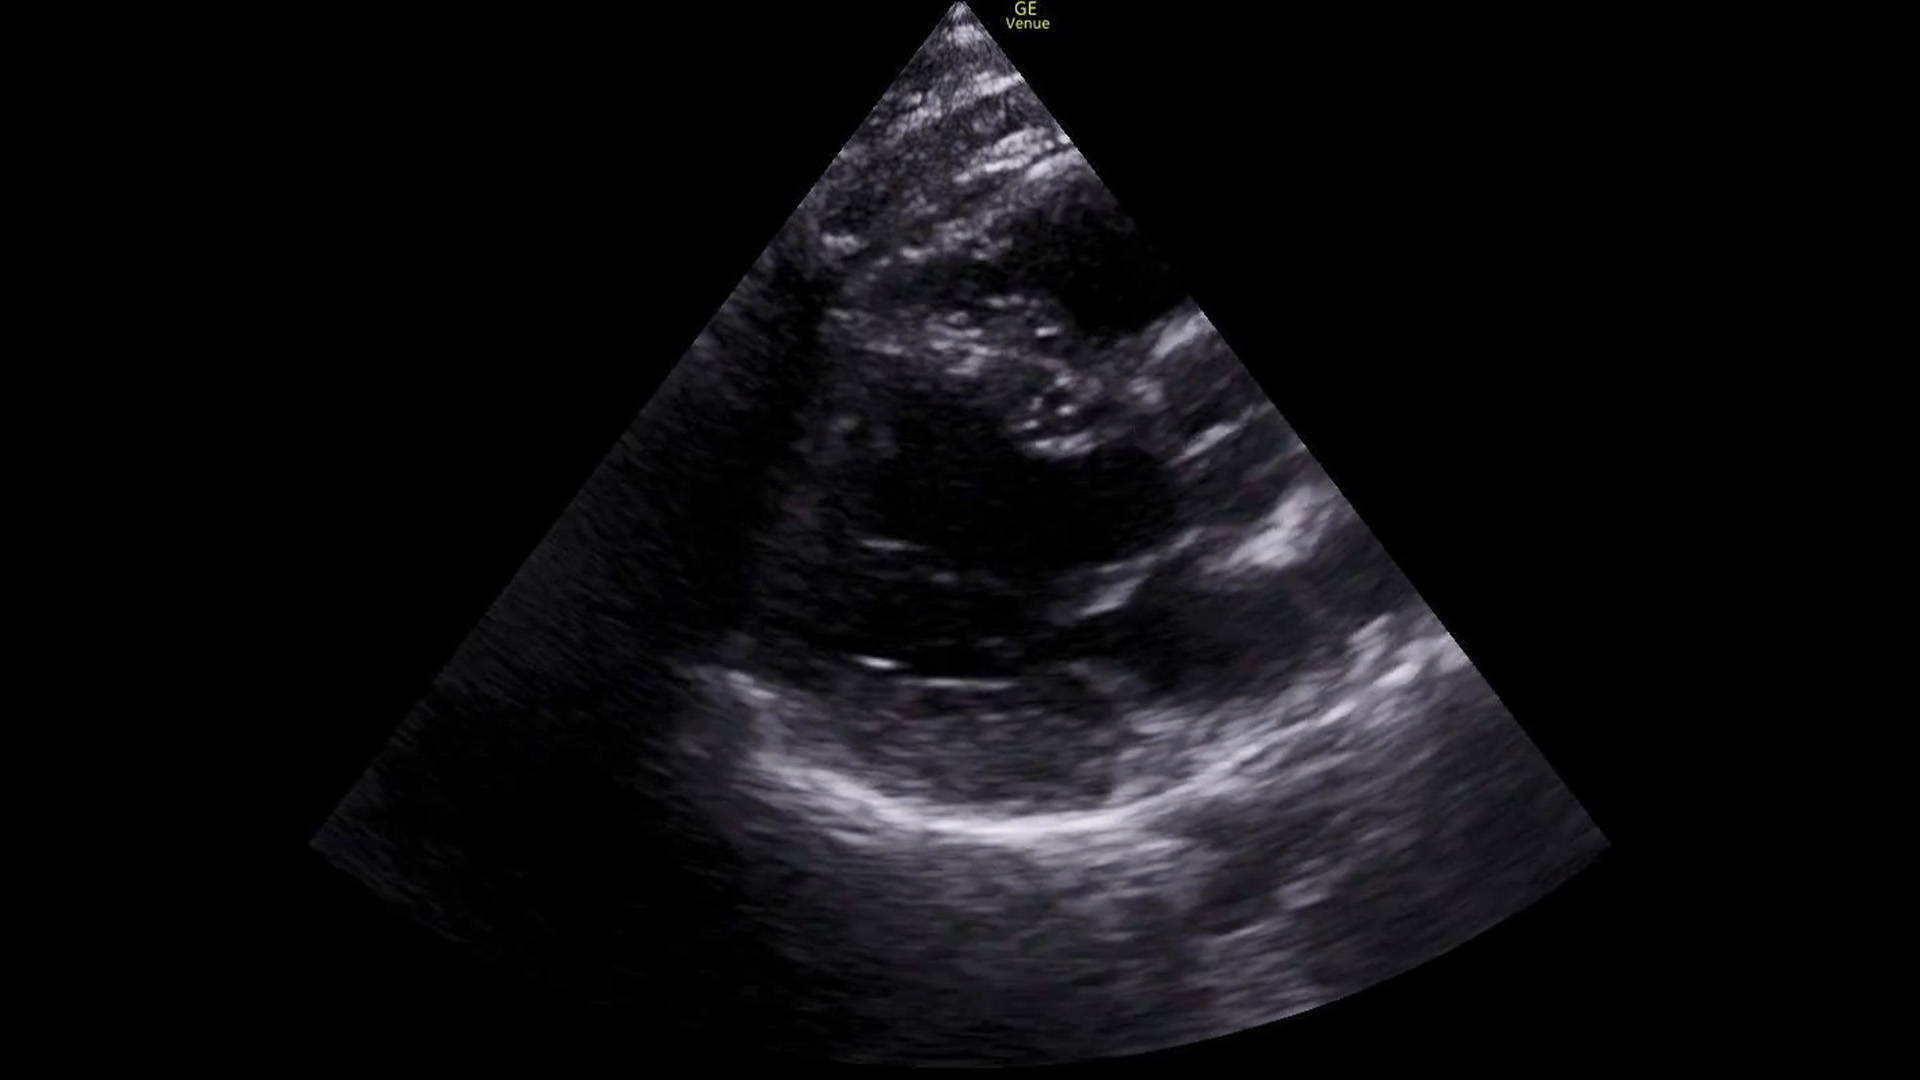

First we get a parasternal long axis view:

We must be able to identify the structures in the image: